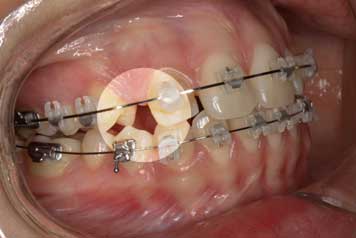

Etapa 1

Tratamiento con ortodoncista, que busca generar el espacio necesario para la correcta ubicación de la pieza ausente.

Implante por Agenesia Dentaria Implante por Agenesia Dentaria